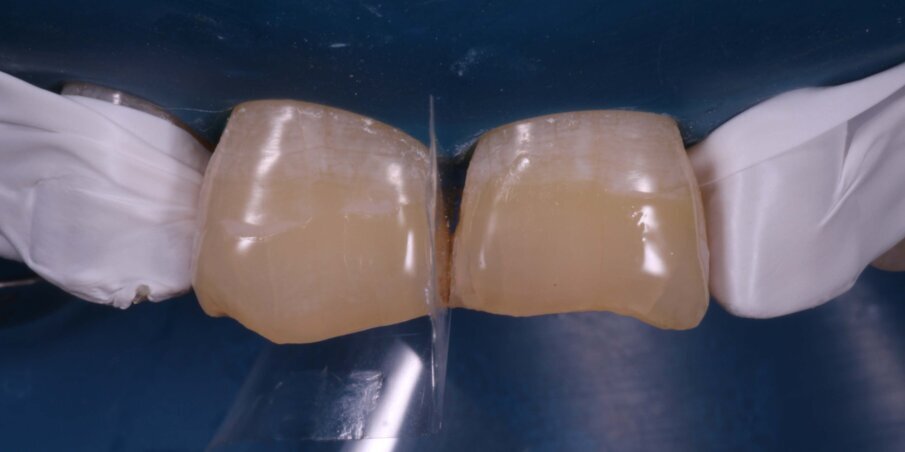

Rubber dam application was carried out (Fig 7) to provide absolute isolation required for the bonding protocol. A 2mm wide bevel was given with a diamond point and finished with finishing discs involving the enamel and dentin on the buccal surface of the fractured teeth. The palatal portion of the fracture line was only smoothened to remove any overhanging enamel. The tooth was etched with 37% Phosphoric Acid (D tech) for 20 seconds (Fig 8). After thorough rinsing with water and light air-drying, two coats of Universal Bonding Agent (Single Bond Universal, 3M ESPE) was applied, air thinned and photocured for 20 seconds (Fig 9).

Fig 7. Isolation with Rubber dam

Fig 8. Etching with 37% Phosphoric Acid

Fig 9. Application of bonding agent